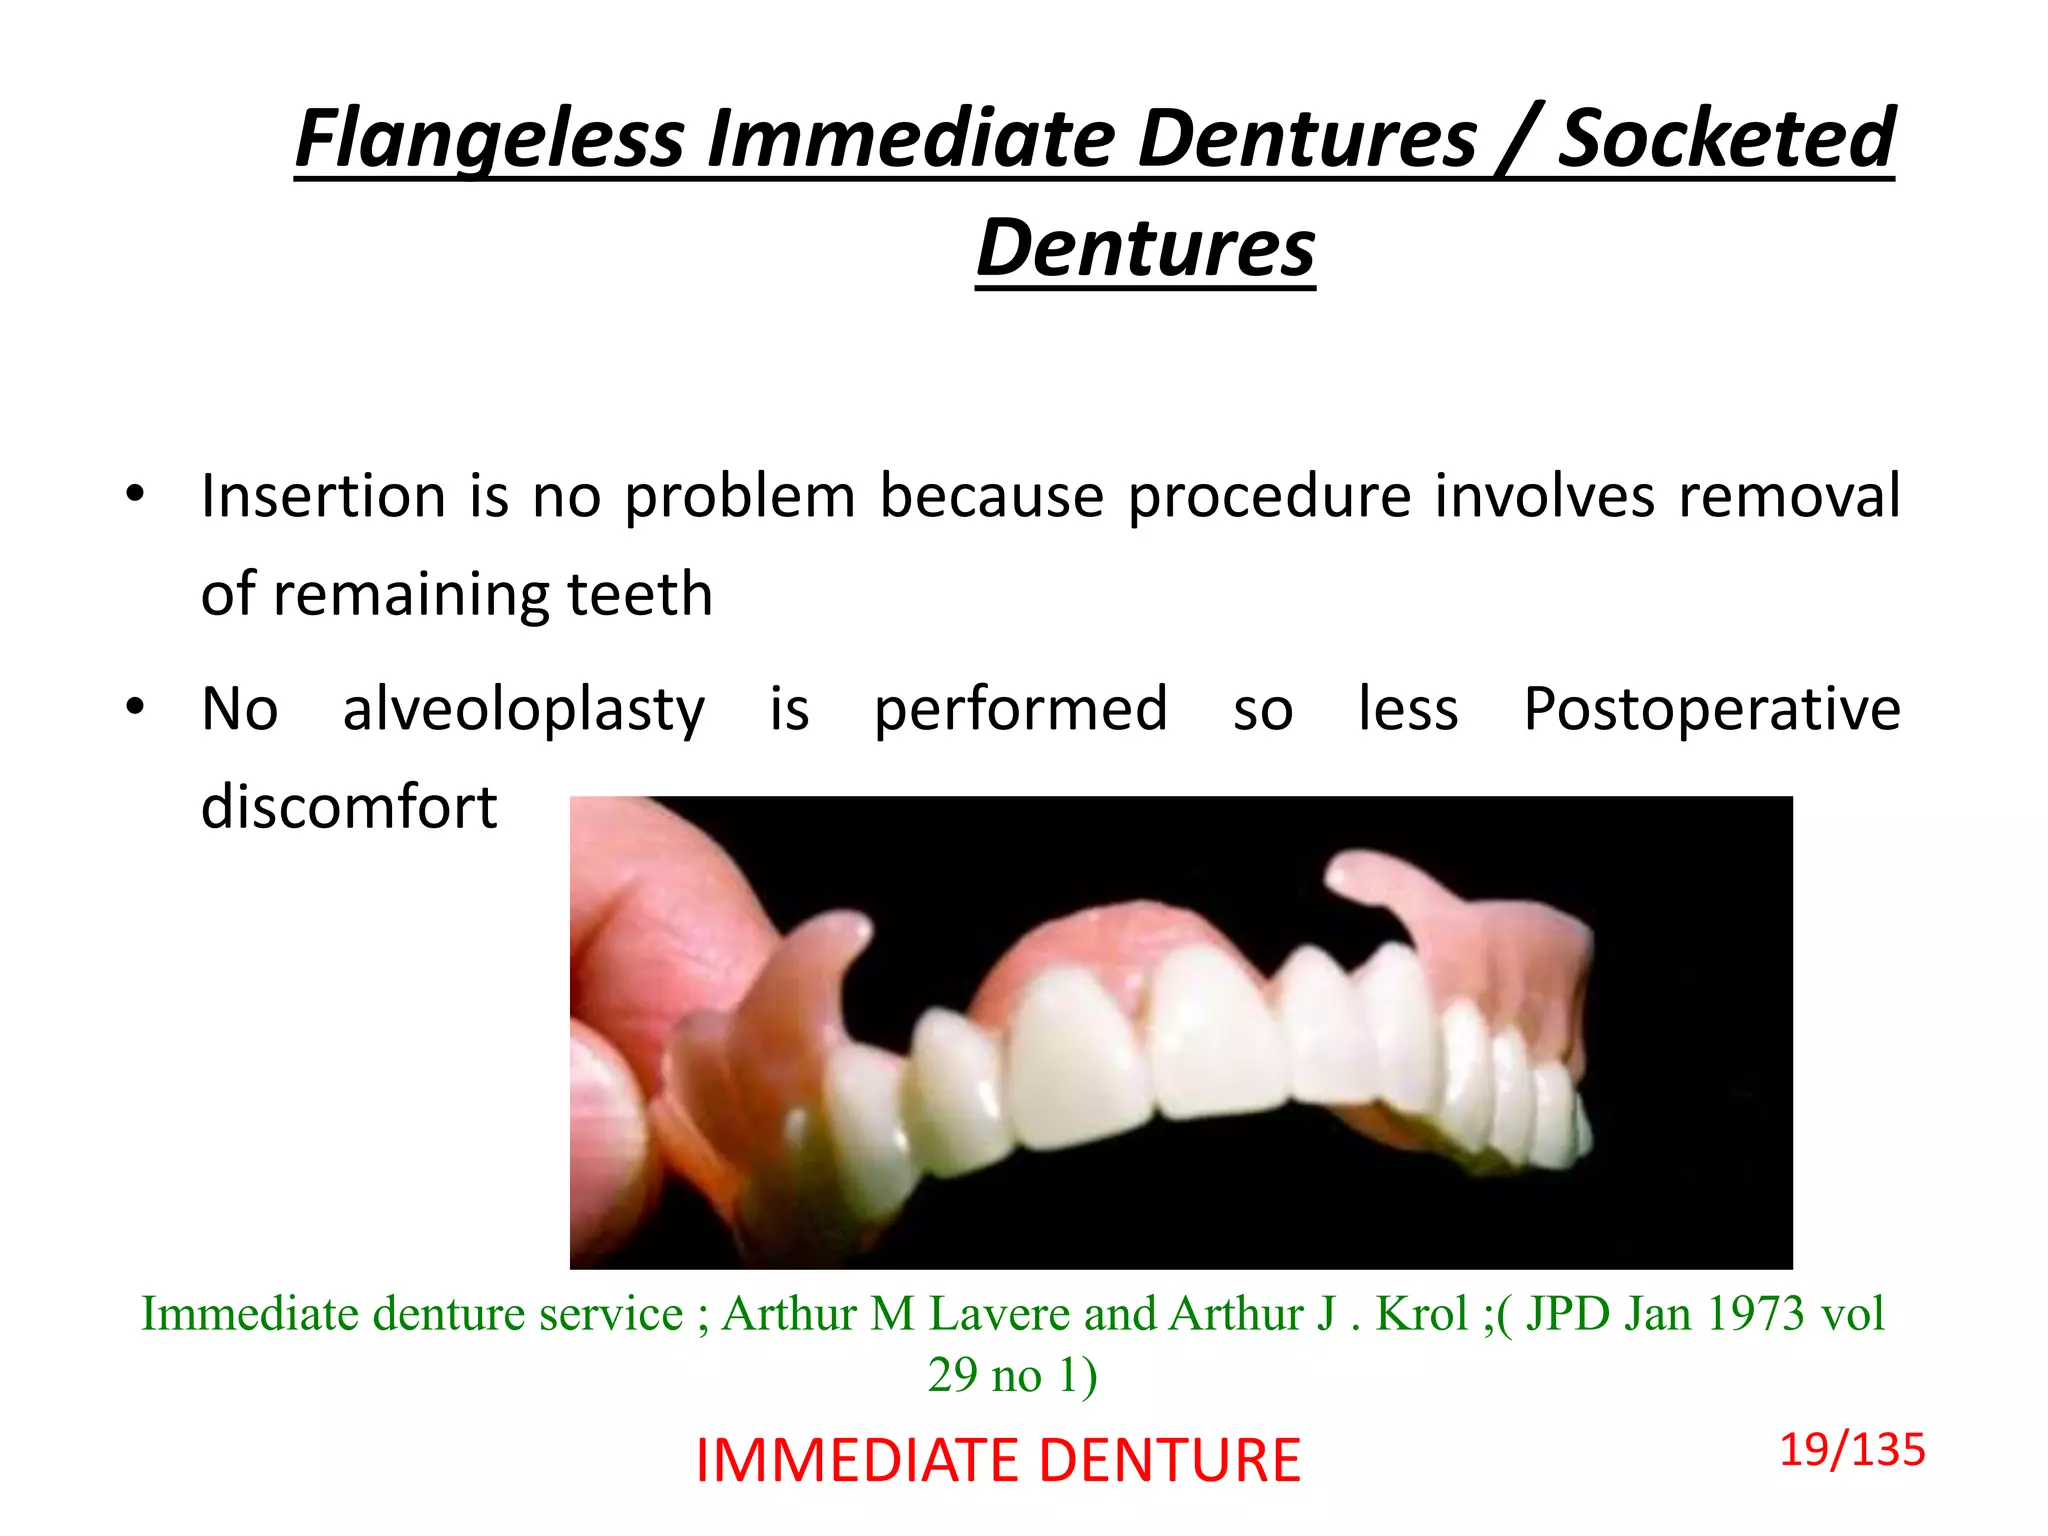

The document discusses immediate dentures, which are dentures fabricated and inserted immediately following tooth extraction. It describes the different types of immediate dentures, including conventional/classic immediate dentures, interim immediate dentures, labial flange dentures, partial flange dentures, and flangeless/socketed dentures. The advantages of immediate dentures include maintaining a patient's appearance without teeth, providing a bandage effect to extraction sites, and allowing easier adaptation to dentures during healing. However, immediate dentures also present challenges like reduced retention from undercuts caused by remaining posterior teeth.